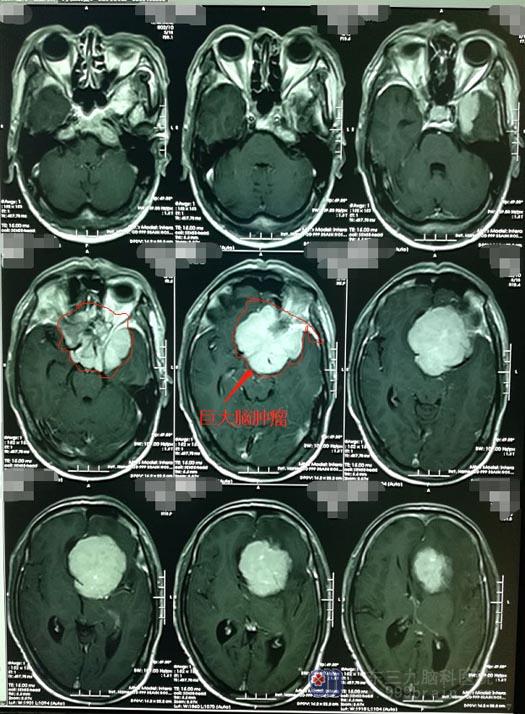

包绕多条颅内动脉的蝶骨嵴巨大脑膜瘤

入住神经外五科后,进一步的影像检查证实石先生是“蝶骨嵴巨大脑膜瘤”,肿瘤巨大,并且包绕了左侧颈内动脉、大脑前、大脑中动脉。

▲术前MR

肿瘤巨大,不但压迫了周围重要的脑组织结构,还包绕了多条颅内动脉及其分支,肿瘤血运特别丰富加上颅内压增高等不利因素,手术全切相当因难,如果不能全切肿瘤,那瘤区的出血将不可想象。手术风险巨大,手术全切肿瘤并保留最佳神经功能是神经外科医生面临的极大挑战。

医院副院长、神经外五科主任带领团队针对患者病情、结合检查结果进行了详细的讨论。先DSA造影,查看颅内血管情况和肿瘤供血动脉,并行球囊压迫实验和allen实验(用于检查侧支循环和尺动脉通畅与否),为术中颅内大血管损伤做搭桥准备。术前准备妥当后,由鲁明主刀实施“左侧蝶骨嵴巨大脑膜瘤术”;术中见病变范围约为6.3cm×6.0cm×5.2cm,病变部分包绕左侧颈内动脉、双侧大脑前动脉、左侧大脑中动脉及左侧视神经等重要结构;将肿瘤全部切除,术中颈内动脉、大脑前动脉、大脑中动脉及视神经保护良好,术中出血约400ml。